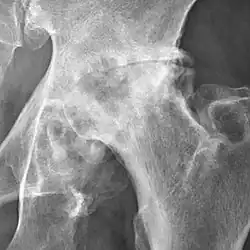

Osteoarthritis of the hip joint may also be graded by Tönnis classification. There is no consensus whether it is more or less reliable than the Kellgren-Lawrence system.[8]

Severe (Tönnis grade 3) osteoarthritis of the hip.

Tönnis classification[9]